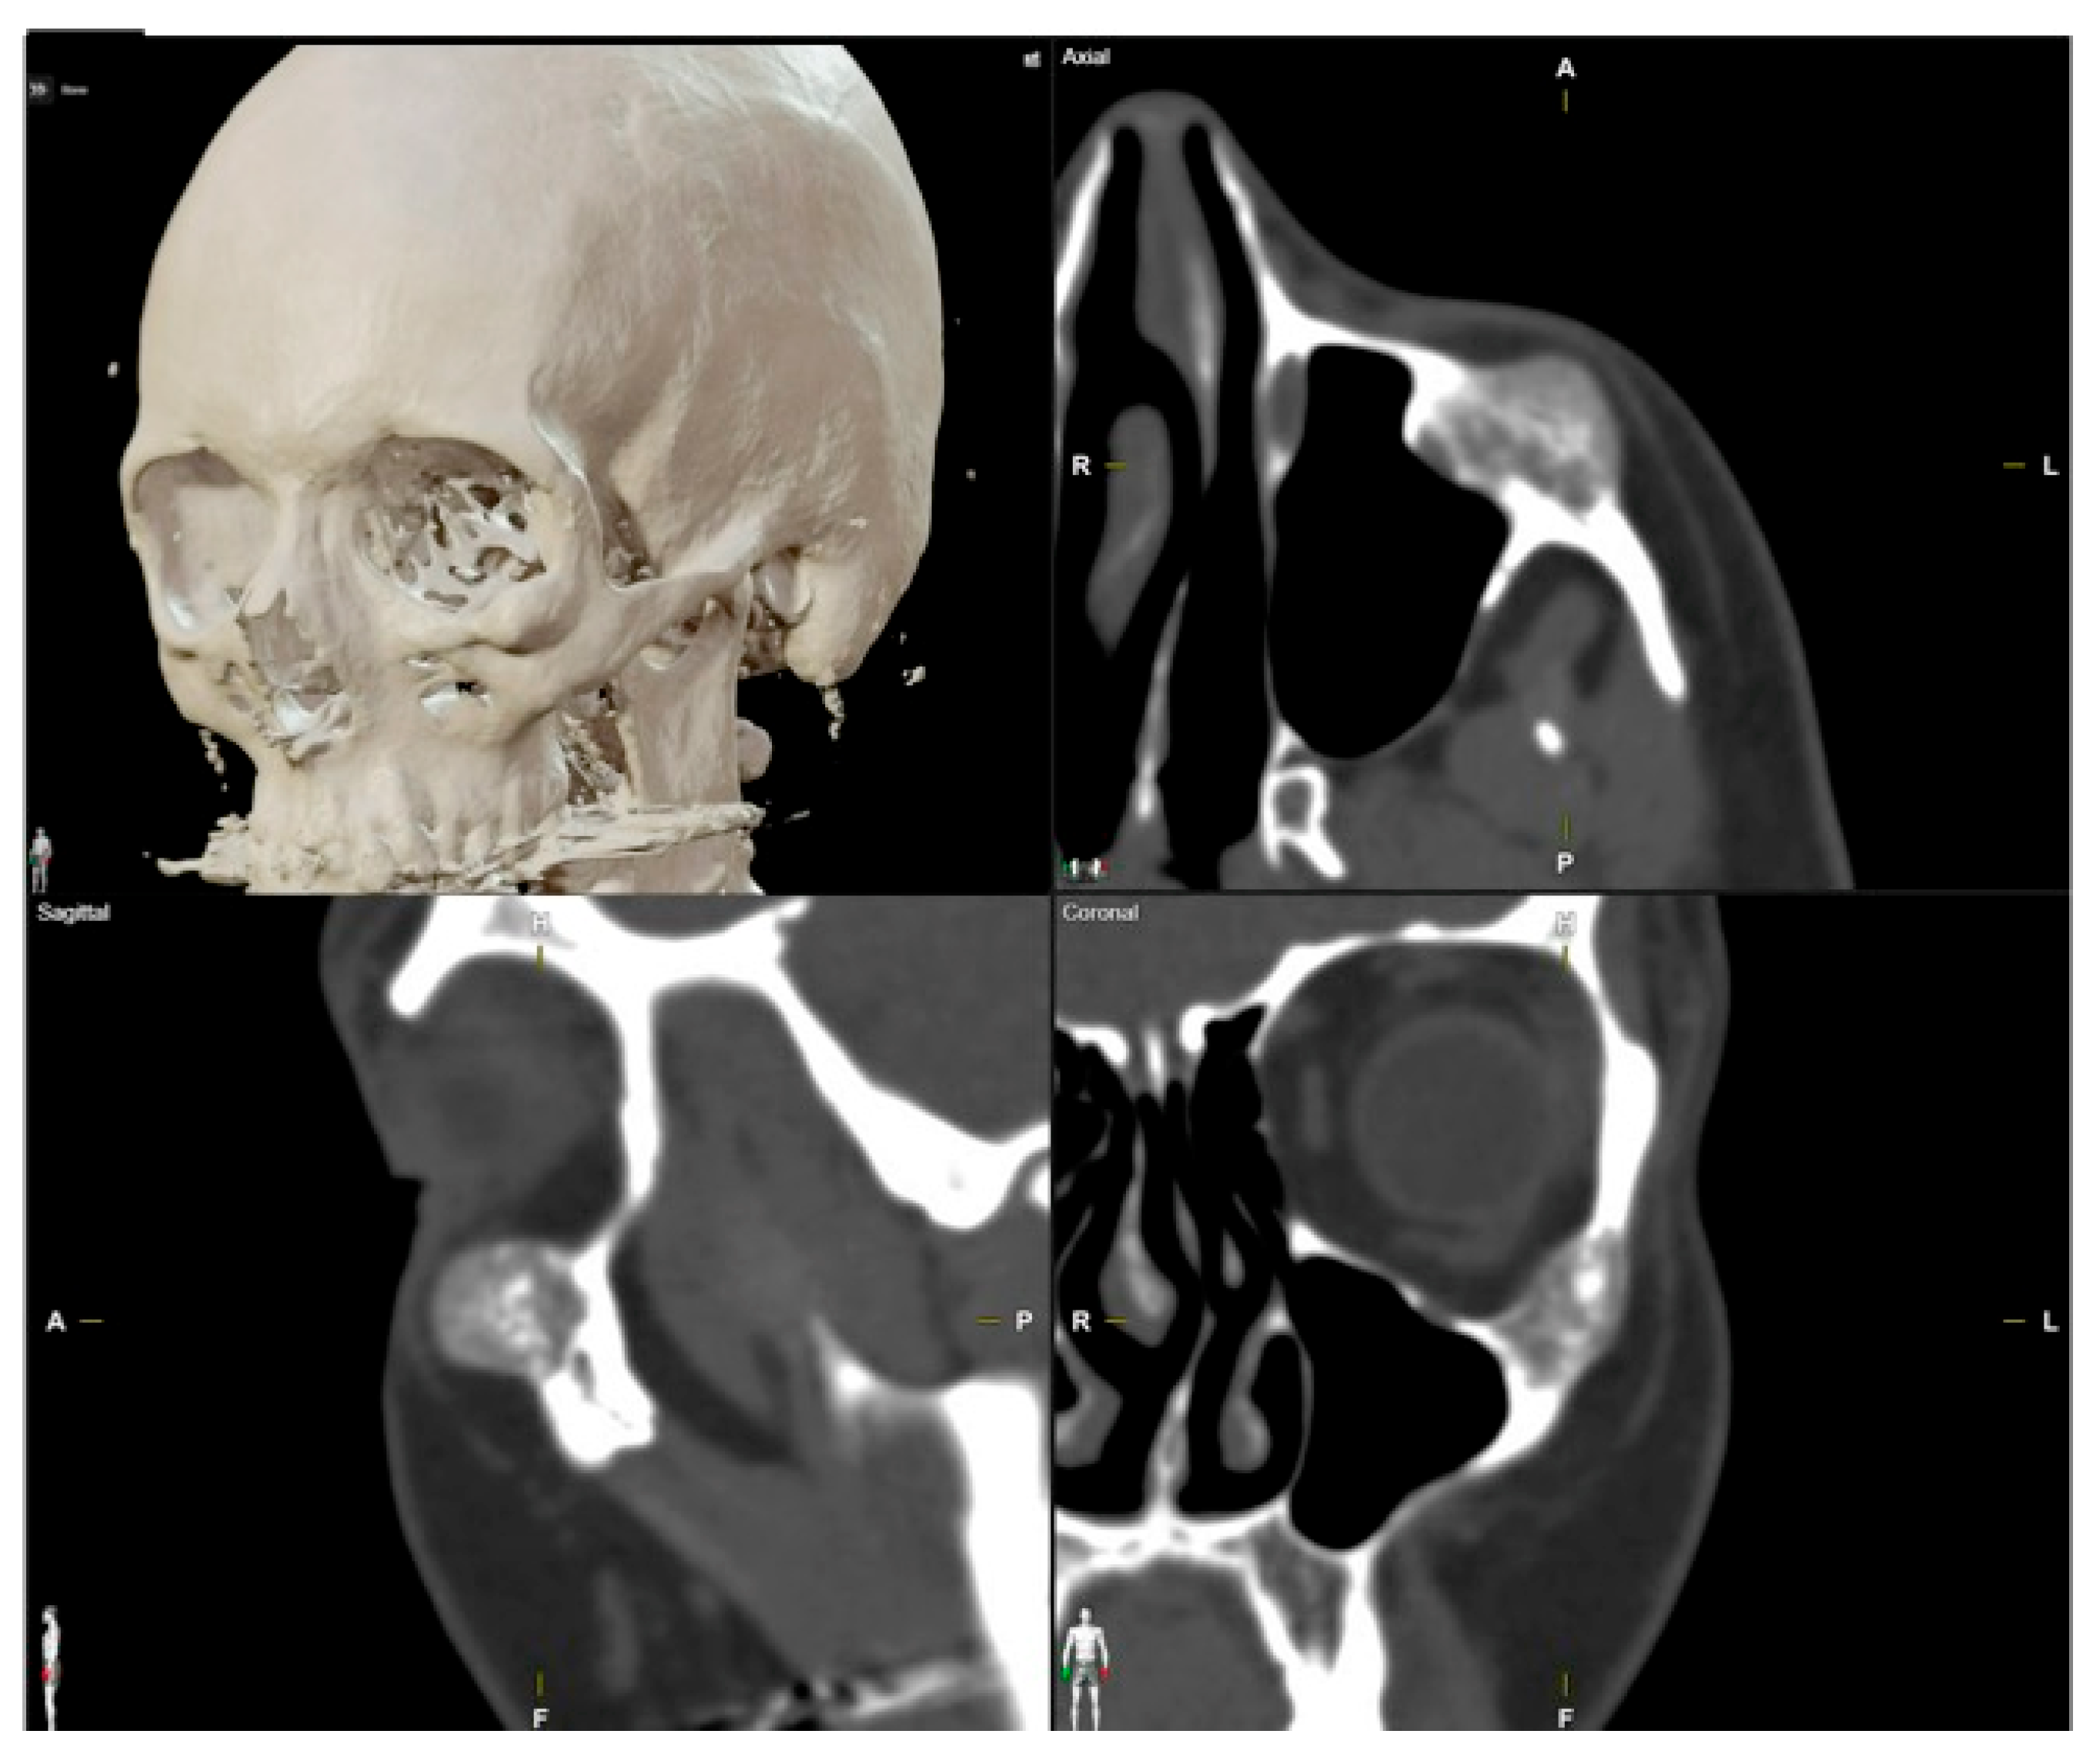

| 3 | 36/F | L/19 mm | Y | 6 mo | N | N | CT, MRI | Zygoma | Arteriovenous malformation | - | Resection + reconstruction | Y | Y | 1st, 2nd, 3rd | Transconjunctival + blepharoplasty + maxillary vestibular | Y | Piezoelectric device | N | PEEK prosthesis | 5 y/N |

| 4 | 47/M | L/30 mm | N | 2 y | N | N | CT | Zygoma | Intraosseous venous malformation | - | Resection + reconstruction | Y | Y | 1st, 2nd, 3rd | Transconjunctival + lateral canthotomy + maxillary vestibular | Y | Piezoelectric device | N | PEEK prosthesis | 6 y/N |